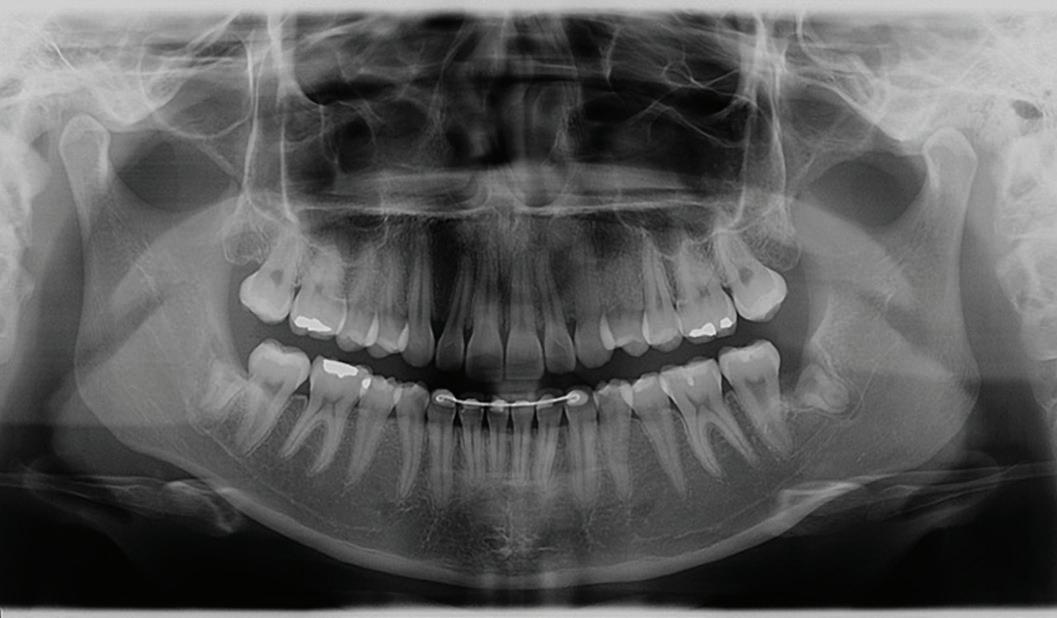

54 Oral and Maxillofacial Surgery

Root migration after coronectomy of impacted mandibular third molars: case reports